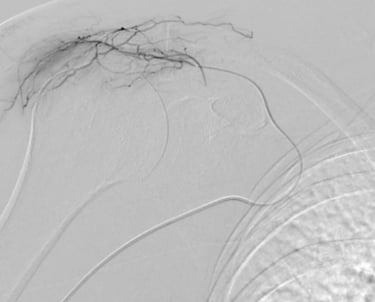

Grâce à l’imagerie de précision (angiographie), le radiologue interventionnel identifie ces vaisseaux « anormaux » et les occlut sélectivement. En bloquant leur flux sanguin, on réduit l’apport en oxygène et nutriments à la zone enflammée, favorisant une régénération rapide des symptômes.

Guidage par imagerie : Le cathéter est avancé jusqu’à l’artère sous-clavière sous contrôle radioscopique en temps réel.

Injection ciblée : Lipiodol dilué dans du produit de contraste iodé est injecté pour boucher les artères pathologiques.

Vérification : Angiographie de contrôle pour confirmer le succès.